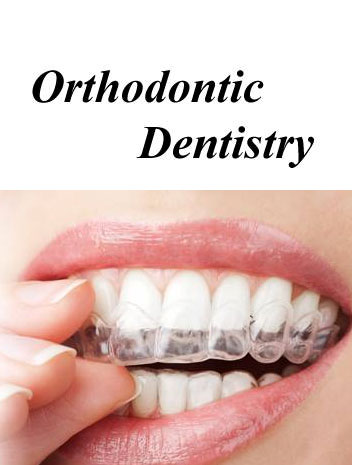

Orthodontics is the branch of dentistry that corrects teeth and jaws that are positioned improperly. Crooked teeth and teeth that do not fit together correctly are harder to keep clean, are at risk of being lost early due to tooth decay and periodontal disease, and cause extra stress on the chewing muscles that can lead to headaches, TMJ syndrome and neck, shoulder and back pain. Teeth that are crooked or not in the right place can also detract from one's appearance.